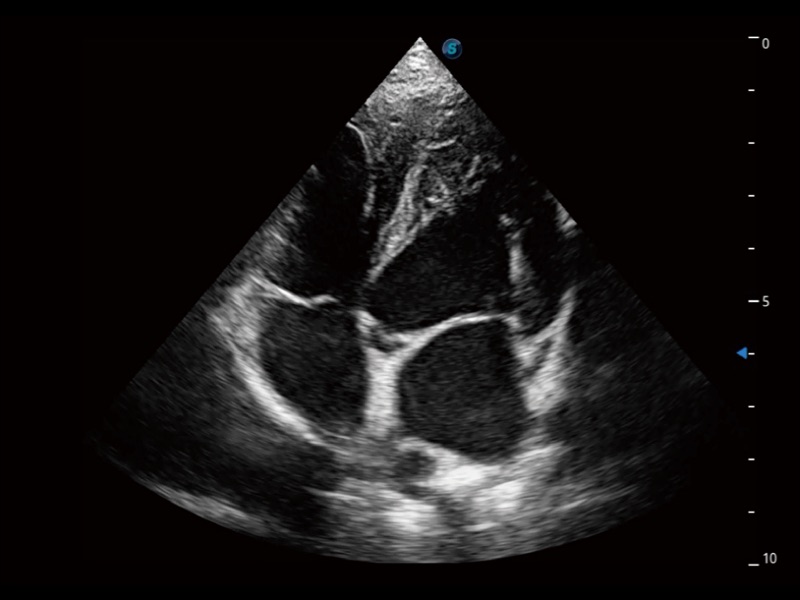

通过创新的 Matrix E自适应滤波器和超长时间域算法,极大提升超低速微细血流的检出能力,同时更精准地滤除软组织和噪声信号,为兽用医生提供以往无法通过常规血流获得的疾病诊断信息。

通过色彩血流和实时宽景相结合,可观察到完整的静脉或动脉的血流,方便医生检查。实时扫查过程中,如有任何操作失误也可以很容易地进行回扫擦除,而不会中断扫查。

ProPet 70专为动物医生设计,对不同的动物体型和生理结构作出了针对性的优化。通过动物影像专用软件,可满足个性化的应用需求,帮助动物医生获得更精确的诊断数据。